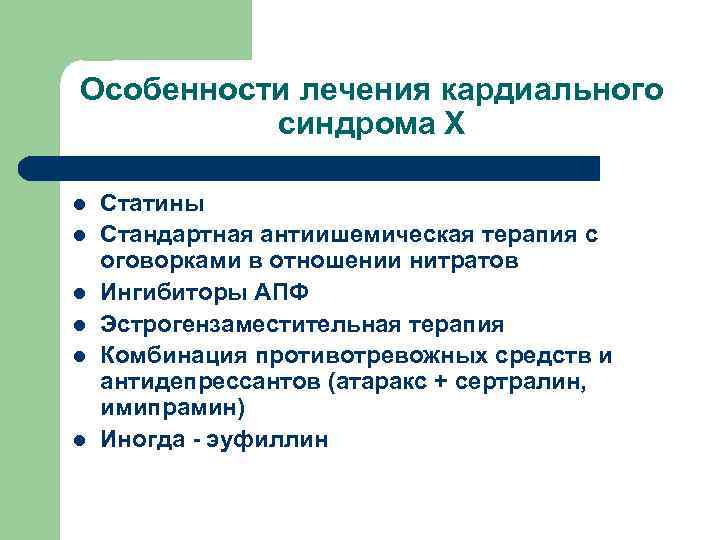

Особенности лечения кардиального синдрома Х l l l Статины Стандартная антиишемическая терапия с оговорками в отношении нитратов Ингибиторы АПФ Эстрогензаместительная терапия Комбинация противотревожных средств и антидепрессантов (атаракс + сертралин, имипрамин) Иногда - эуфиллин